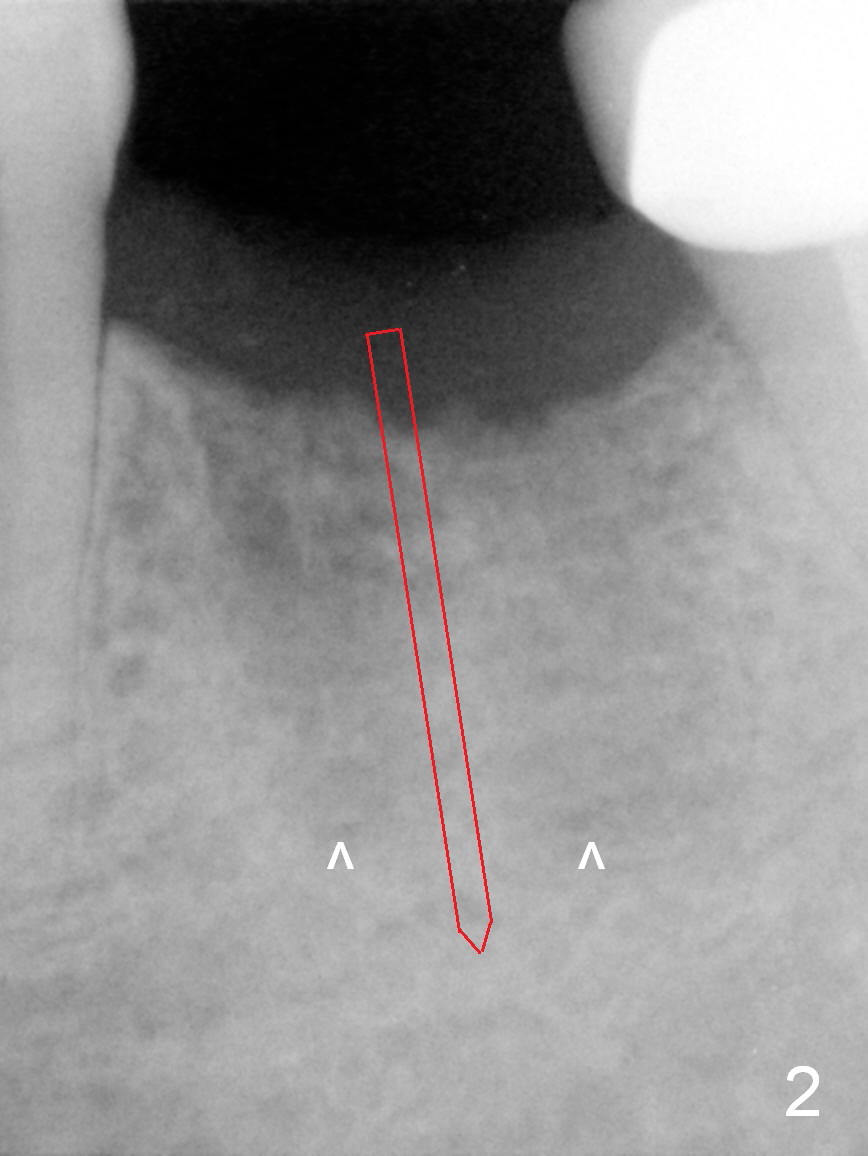

A 68-year-old man had the tooth #19 extracted more than 6 months ago (Fig.1). When his wife has had an immediate implant placed, he decides to have his implant placed. After incision, use the 5 mm implant positioner to check the width of the crestal bone. If it is less than 6 mm, the implant length will be most likely 14 mm. Clinical exam has revealed moderate ridge atrophy. Anyway, the initial osteotomy is 12 mm. It should pass the apices of the mesial (M) and distal (D) sockets (Fig.2 ^) in the middle of the septum (as compared to Fig.1 S). If there is enough safety margin, the osteotomy depth will be set at 14 mm (Fig.3 (red dashed line: the superior border of the Inferior Alveolar Canal)). There is no indication for intraop localized use of antibiotic.